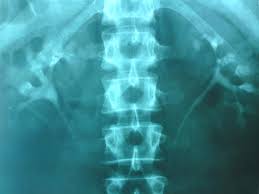

«Το ΙΔΕ ή ΙΠ υποχρεούται να τηρεί πλήρως τους κανόνες υγιεινής και ασφάλειας για την διασπορά των λοιµώξεων, την προστασία από επικίνδυνες ακτινοßολίες, την ασφαλή αποθήκευση επικίνδυνων ουσιών και να διατηρεί τα µηχανήµατα και τα αναλώσιµα υλικά τους στο καλύτερο δυνατό επίπεδο λειτουργίας και ασφάλειας. Επιπλέον, κατ’ εφαρµογή του άρθρου 34 του Ν. 4025, το ΙΔΕ ή ΙΠ υποχρεούται, εντός δύο ετών, να εφαρµόζει αποδεδειγµένα µεθόδους εσωτερικού ποιοτικού ελέγχου και να λαµßάνει µέρος σε προγράµµατα εξωτερικού ποιοτικού ελέγχου που εφαρµόζονται από πιστοποιηµένους ιδιωτικούς ή δηµόσιους φορείς που λειτουργούν στην Ελλάδα ή στο εξωτερικό για όσες εξετάσεις εκτελεί και για τις οποίες υπάρχει δυνατότητα ποιοτικού ελέγχου. Επιπρόσθετα, υποχρεούται, εντός του ως άνω διαστήµατος, να πιστοποιηθεί µε αναγνωρισµένο σχετικό πρότυπο. Το ΙΔΕ ή ΙΠ θα πρέπει να τηρεί και ηλεκτρονικό αρχείο των παρεχοµένων υπηρεσιών που πραγµατοποιεί για τους ασφαλισµένους του Ταµείου. Σε αντίθετη περίπτωση δεν θα αποζηµιώνεται εντός των προßλεπόµενων προθεσµιών. Συµφωνείται ότι µε την ολοκλήρωση της εφαρµογής των διατάξεων του Ν.3892/2010 το ΙΔΕ ή ΙΠ υποχρεούται να διαθέτει τον απαραίτητο εξοπλισµό του συστήµατος ηλεκτρονικής συνταγογράφησης παρακλινικών εξετάσεων. Επιπλέον, εντός δύο ετών πρέπει να διαθέτει σύστηµα Διαχείρισης και Αποθήκευσης Ιατρικής Απεικόνισης εικόνας ικανό να διατηρήσει πλήρες και άµεσα ανακτήσιµο ιστορικό εξετάσεων σε ßάθος 10 ετών. Στο σύστηµα αυτό θα έχουν πρόσßαση τα εξουσιοδοτούµενα προς τούτο Όργανα του Ταµείου µέσω κοινού προσωπικού υπολογιστή, είτε τοπικά, είτε και διαδικτυακά».

Α) Συµßεßληµένα αυτοµάτως µε την έναρξη λειτουργίας του ΕΟΠΥΥ είναι τα εργαστήρια των Νοσοκοµείων, Κέντρων Υγείας και ΙΚΑ αλλά πουθενά δεν έχει εξ΄όσον γνωρίζω αναφερθεί ότι πρέπει να προσαρµοστούν και αυτά ως προς την πιστοποίηση (ISO και εξωτερικός ποιοτικός έλεγχος) και τη διάθεση συστήµατος διαχείρισης εικόνας και προφανώς δεν το απαιτεί διότι οι ιθύνοντες γνωρίζουν ότι η πλειοψηφία αυτών δεν δύναται να πιστοποιηθεί (παλαιότερα µηχανήµατα, ανύπαρκτη µηχανογράφηση και τη δυσκολία απόκτησης και διαχείρισης των συστηµάτων µεταφοράς και αποθήκευσης εικόνας).